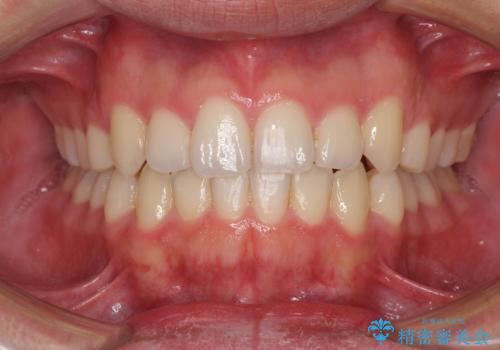

狭い歯列と前歯のデコボコ インビザラインによる矯正治療

- 上下前歯のデコボコを気にして来院された患者様です。

インビザラインによる上下歯列の拡大と、IPR(歯と歯の間を削る)にるスペースの獲得により、前歯のデコボコと狭い歯列を改善することとしました。

比較的軽度な歯列不正であったため、治療期間はそれほど長くはならないと予想されました。

しかしながら、あまりしっかりとマウスピースを装着していなかったため、思いの外期間が長引いてしまいました。

また、仕上がりの歯列にも若干の叢生が残ってしまいました。